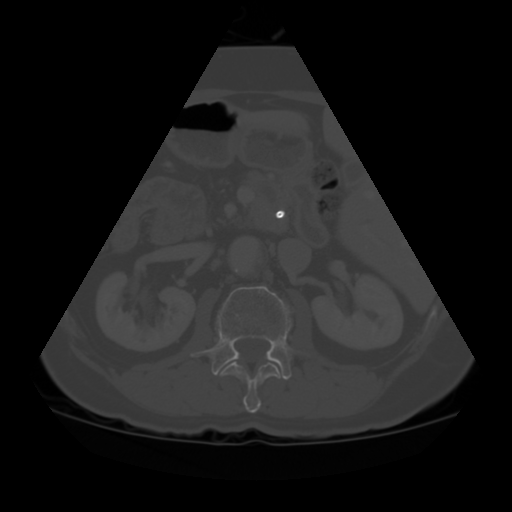

The Abdomen-1K dataset provides more than 1000 CT scans, and the data is provided in 3D format. Firstly, we randomly select 200 CT scans, and for each CT scan, we randomly sampled 10 transverse plane slices. For a more uniform image shape, we applied a fan shape mask to the CT images to mimic the outline of convex ultrasound images.

Fig. 5 and 6 present examples of the translation results from CT to ultrasound. These visual comparisons demonstrate that the S-CycleGAN can not only mimic the ultrasound style but also preserve critical anatomical features compared with Fig. 3. The synthetic images closely resemble real ultrasound scans in terms of texture and shape, suggesting a high level of detail preservation.

Refer to caption

(a) Real CT

(b) Fake US

(c) CT Label

(d) Predicted US Mask

Figure 6: CT-to-ultrasound translation example.2